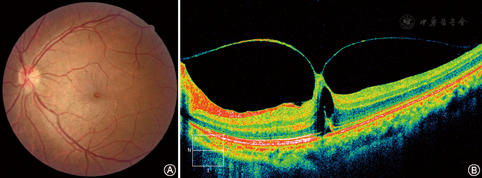

患者男性,44岁。因左眼视力下降伴视物变形1个半月,就诊于天津市眼科医院。眼部检查:左眼视力0.4,无法矫正;左眼前节检查无明显异常;眼底检查情况见精粹图片中1中A。使用美国Optovue RTVue XR100-2型OCT检查仪行左眼OCT检查,情况见精粹图片中1中B。使用MD-2300型A/B超声波仪行左眼超声检查,显示黄斑部视网膜呈中等回声隆起,表面粗糙。临床诊断:左眼玻璃体黄斑牵拉综合征。

左眼玻璃体黄斑牵拉综合征患者眼底检查图像A示左眼彩色眼底图像,可见以黄斑区中央为中心的放射状皱褶达到上下血管弓附近,黄斑中心凹区呈圆形橘红色改变;B示左眼相干光断层成像术图像,可见不完全的玻璃体后脱离呈V形,黄斑中心凹的玻璃体与视网膜粘连紧密,玻璃体黄斑牵拉,黄斑中央区可见低反光的囊腔,其下的视网膜光感受器内外节链接层及视网膜色素上皮层部分缺失